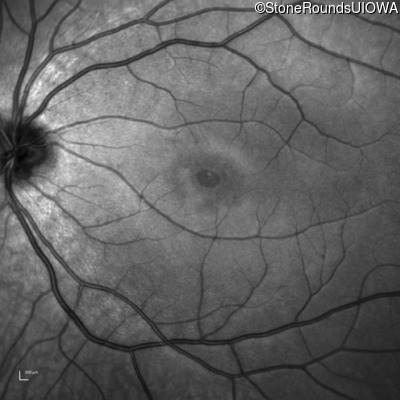

Infrared Fundus Photograph - Right - 20/160 +2

Exemplar